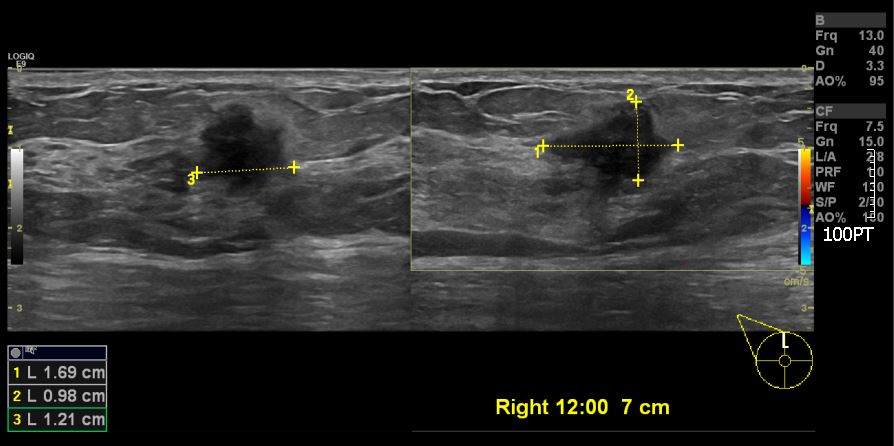

우측유방에 만져지는 멍우리로 내원하신 50대 환자분이십니다.

본원에서 우측12시 방향에 혹을 조직검사 시행하였고

결과상 침윤성 유관암 진단되었습니다.